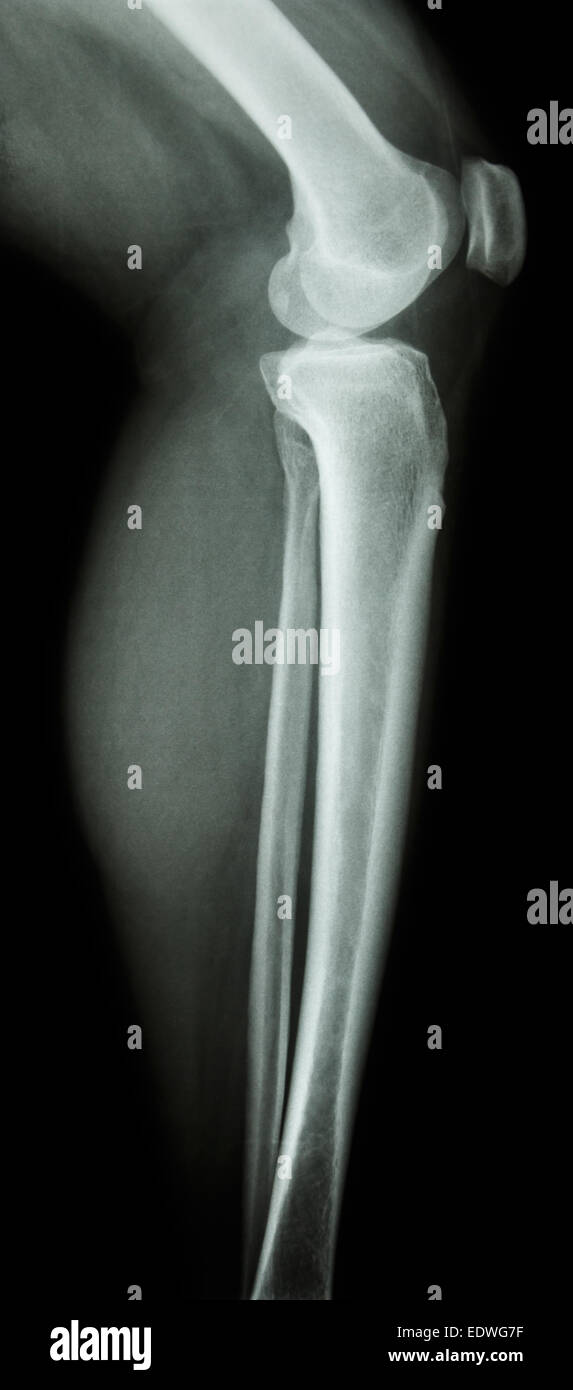

Film x-ray latérale du genou : le genou humain normal-leg Banque D'Imageshttps://www.alamyimages.fr/image-license-details/?v=1https://www.alamyimages.fr/photo-image-film-x-ray-laterale-du-genou-le-genou-humain-normal-leg-77393555.html

Film x-ray latérale du genou : le genou humain normal-leg Banque D'Imageshttps://www.alamyimages.fr/image-license-details/?v=1https://www.alamyimages.fr/photo-image-film-x-ray-laterale-du-genou-le-genou-humain-normal-leg-77393555.htmlRFEDWG7F–Film x-ray latérale du genou : le genou humain normal-leg